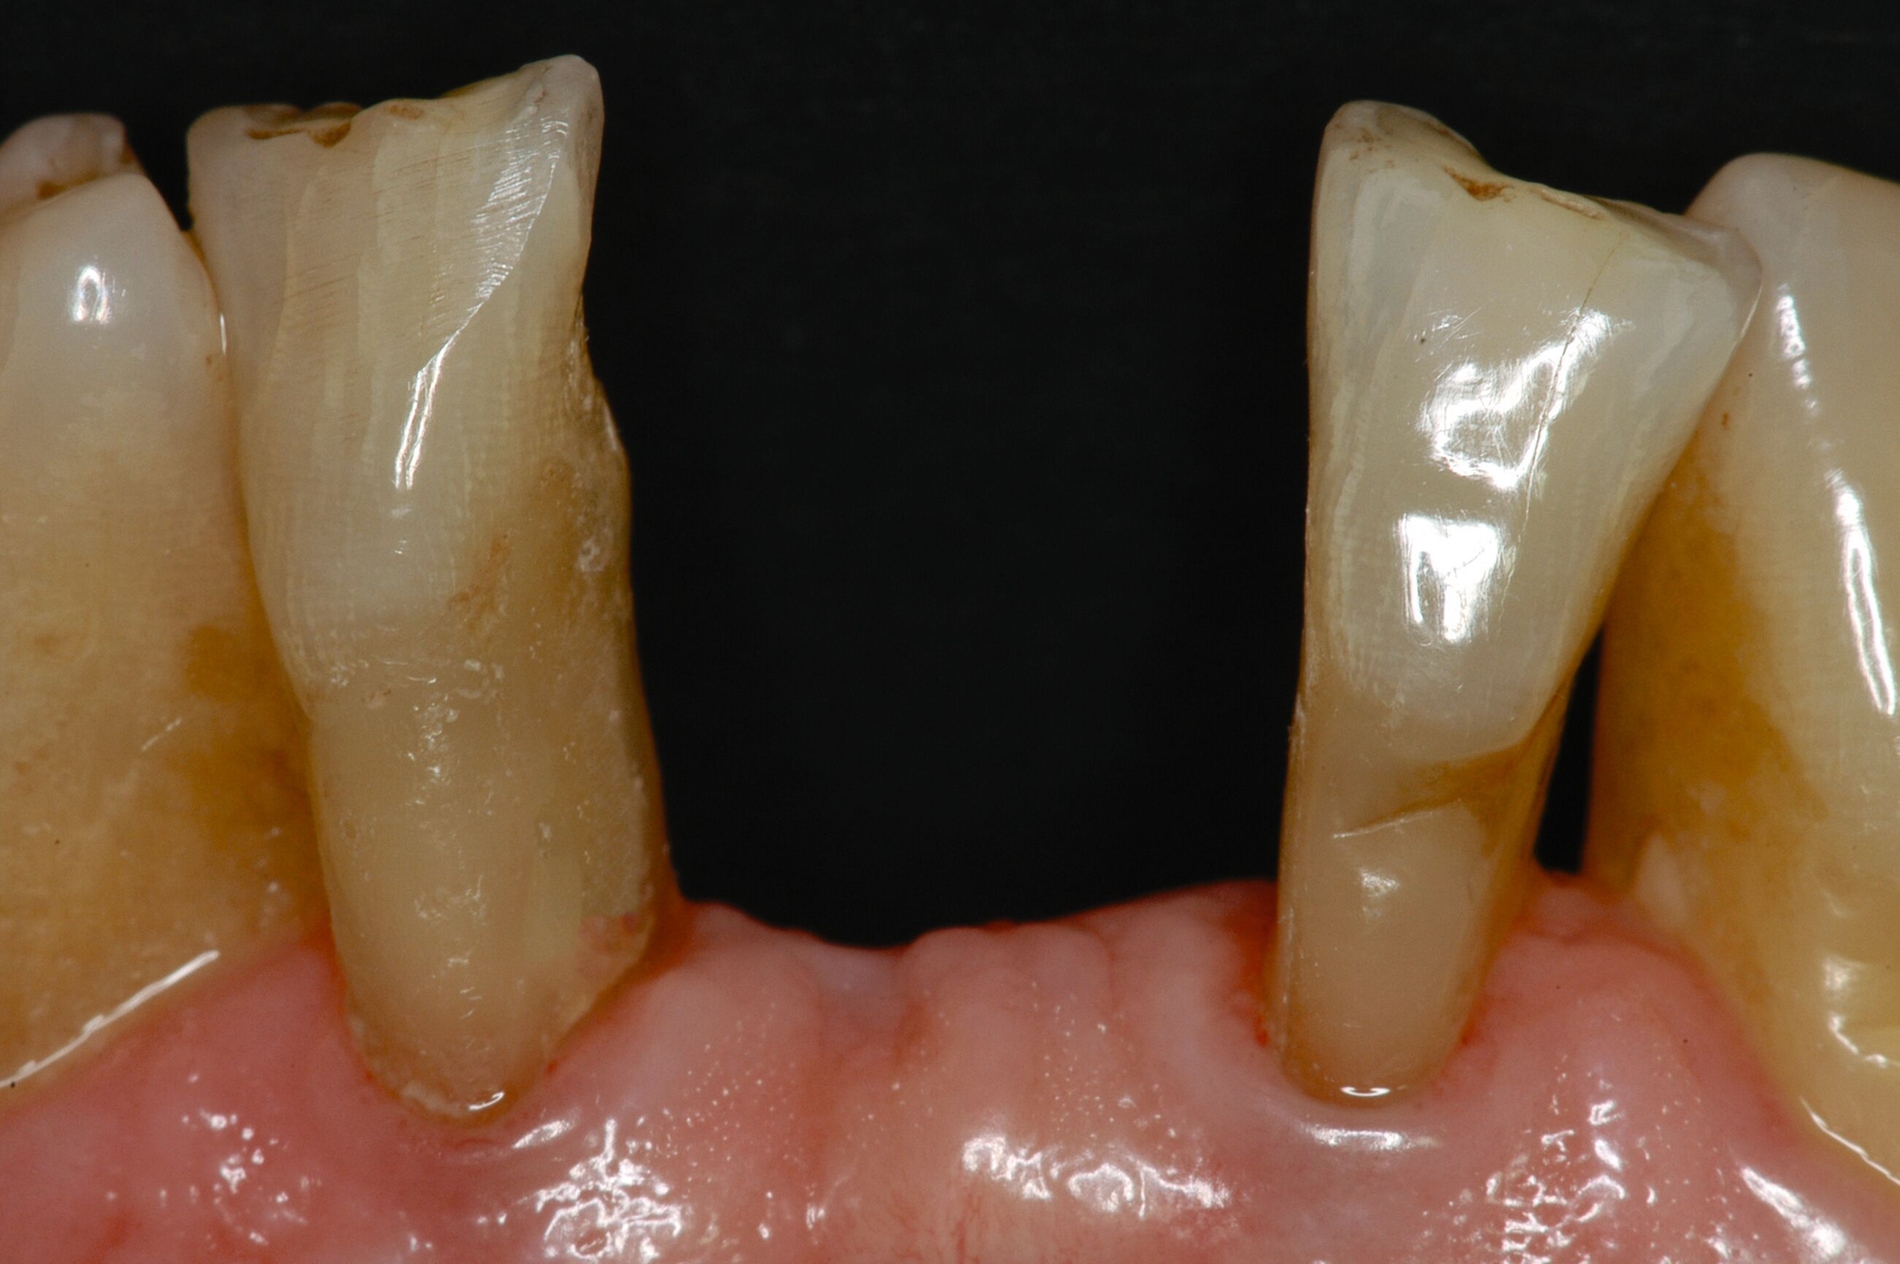

Ein Ersatz der Molaren war nicht erforderlich, da der Patient mit der verkürzten Zahnreihe seine Kaufunktion als ausreichend empfand. Aufgrund der erhöhten Beweglichkeit der Oberkieferfrontzähne, die die mundgesundheitsbezogene Lebensqualität stark beeinträchtigte, wurde eine adhäsive Schienung von Zahn 13 bis 21 durchgeführt. Dabei kam ein Polyethylen-Fasernetz (Ribbond, Seattle, USA) zum Einsatz (Abbildung 10). Zur Versorgung der Freiendsituation wurden zwei Implantate mit lokalem Knochenaufbau inseriert und mit implantatverankerten zementierten Einzelkronen versorgt. Die Frontzahnschaltlücke im Unterkiefer wurde mit zwei einflügeligen Adhäsivbrücken aus labial verblendeter 3Y-TZP-Zirkonoxidkeramik (Abbildungen 11 bis 13) geschlossen, die Schaltlücken regio 44 und 46 durch eine Anhängerbrücke, die von Zahn 47 bis Zahn 44 reichte (Abbildung 14).

Der Patient konnte über einen Zeitraum von mehr als 20 Jahren nachbeobachtet werden. In den ersten 14 Jahren stellte er sich jährlich in der Klinik zur unterstützenden Parodontitistherapie und Kontrolle der Restaurationen vor (Abbildung 15). Der parodontale Zustand konnte stabil gehalten werden und auch die prothetischen Versorgungen erwiesen sich komplikationsfrei.